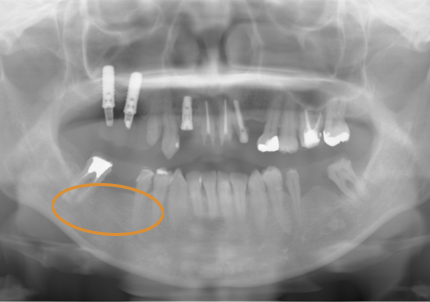

24.パノラマレントゲン

↑2006年4月24日(初診時)

↑2024年6月26日

25.初診より18年経過(2024年6月26日)